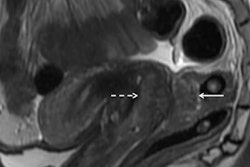

In a new study, Belgian researchers found that MRI can predict the severity of endometriosis in women referred for surgery when it is used as a complement to transvaginal ultrasound. Results were published online on 10 September in Ultrasound in Obstetrics & Gynecology.

Bielen and colleagues' study included 74 patients with clinically suspected endometriosis with urological and intestinal involvement who were referred for surgery between 2014 and 2015. All of the women underwent transvaginal ultrasound, DCBE, IVU, and abdominal MRI; gynecologists performed the ultrasound exams, while radiologists performed the DCBE, IVU, and MRI exams.

The combination of transvaginal ultrasound and MRI was correct in 86.5% of patients for assessing involvement of the bowel wall, gynecological structures, bladder, and ureters, the researchers found. The combination of transvaginal ultrasound, IVU, and DCBE was correct in 67.6% of patients (p = 0.02).